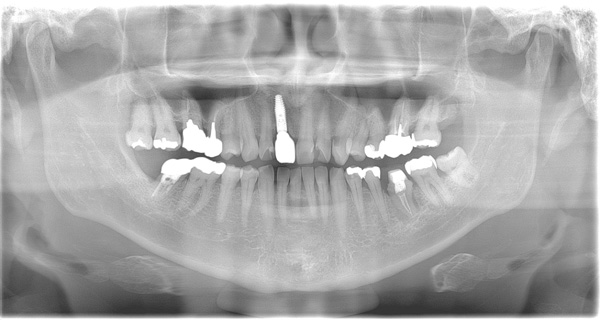

| 年代・性別 | 50代 男性 |

|---|---|

| 主訴 | 前医で前歯を抜かなければならないがインプラントはできないと言われた |

| 治療期間 | 約12ヶ月 |

| 費用 | 600,000円 |

| 治療内容 | インプラント、骨造成、結合組織移植、セラミック修復 |

| 治療に伴うリスク | インプラント周囲炎 セラミックの破折、脱離 |